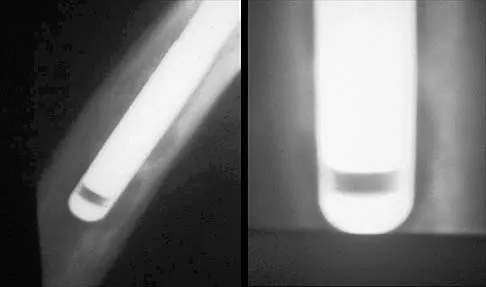

Figure 33 shows the AP and lateral radiographs of an obese 58-year-old man who underwent a cementless total hip arthroplasty 6 years ago. He reports no pain, and examination reveals a normal gait and painless hip range of motion. What is the most likely diagnosis?

Explanation